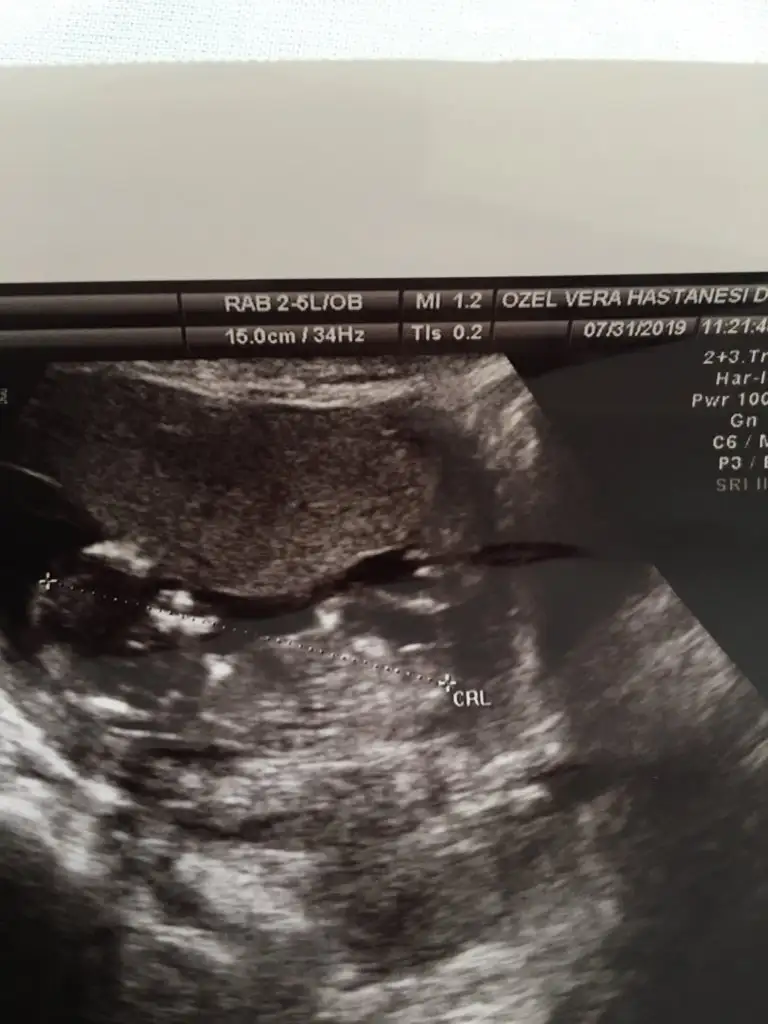

11 haftalık 🤗tahmin alabilirmiyim

• E4176EC0-6CEF-472E-9E6B-7076816D4CA5.webp

E4176EC0-6CEF-472E-9E6B-7076816D4CA5.webp

14,2 KB · Görüntüleme: 50